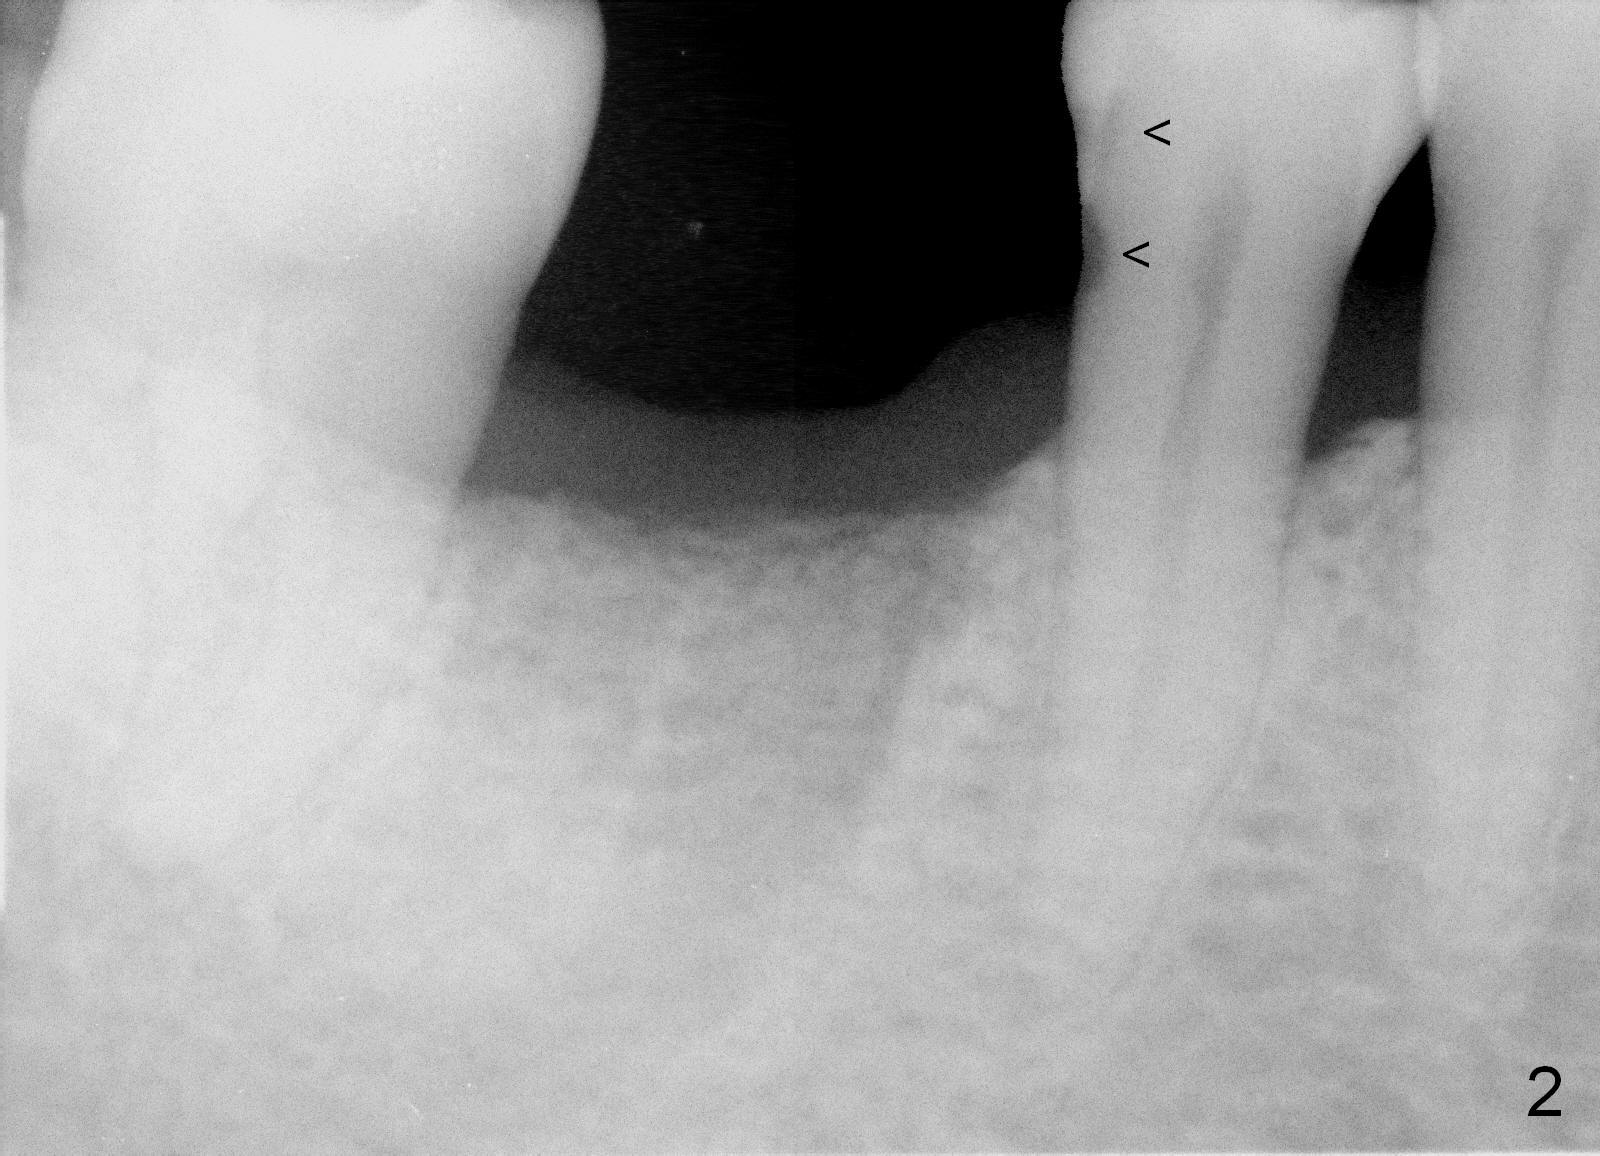

A 44-year-old man lost the tooth #30 three months ago. He is very nervous about the Inferior Alveolar Nerve (Fig.1,3 yellow dashed line). Offer Valium if needed. Check whether there is DO caries of the tooth #29 (Fig.2 <). Finish composite if indicated. There is mild to moderate buccal plate atrophy. The implant may have to be placed slightly lingually. When the insertion torque is high, place an abutment (Fig.3 white inverted cup) with subgingival margin (arrowheads: gingival margin) so that the emergency profile of the crown is better. Make an ideal immediate provisional with good emergency profile and place sutures. The mesial bone may have to be trimmed (Fig.4 red area) so that the abutment is able to be seated without interference. Take photo at each step.